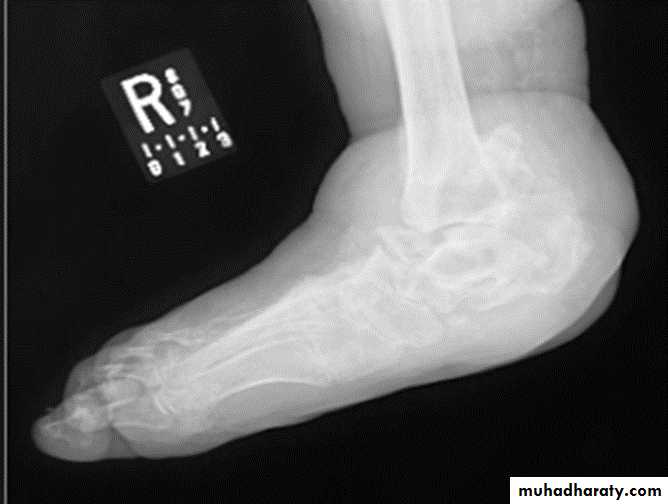

NEUROPATHIC ARTHRITIS (CHARCOT'S JOINT)

Primary loss of sensation in a joint leads to arthropathy. Distribution helps determine etiology.Causes

Diabetes neuropathy: usually foot

Tertiary syphilis : usually knee

Syringomyelia: usually shoulder

Radiographic features:

Common to all types

*Joint instability: subluxation or dislocation

*Prominent joint effusion

--- Hypertrophic type, 20%

Marked fragmentation of articular bone

Much reactive bone

--- Atrophic type, 40°/0

Bone resorption of articular portion

--- Combined type, 40%